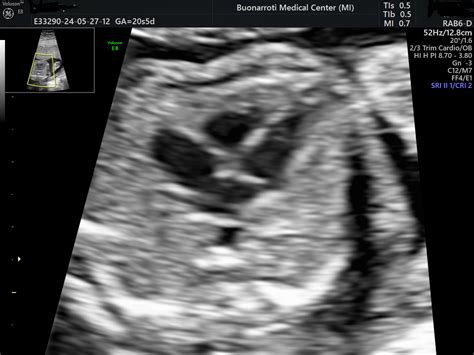

A differenza delle ecografie ostetriche generiche, l'ecocardiografia fetale è uno studio mirato e approfondito dell'anatomia e della funzionalità cardiaca del feto all'interno dell'utero materno. Utilizzando ultrasuoni e tecnologie avanzate come il Doppler colore e spettrale, permette di valutare la struttura del cuore, le cavità cardiache, le valvole, i grossi vasi e il flusso sanguigno.

Durante l'ecocardiografia fetale, il medico esperto appoggia una sonda ecografica sull'addome materno, ricercando scansioni ottimali per lo studio del cuore fetale. Utilizzando la tecnologia Doppler colore, vengono analizzate la direzione e la modalità del flusso sanguigno nelle cavità cardiache. Il Doppler spettrale può essere impiegato per misurare le velocità del flusso, se necessario. In alcuni casi, per una valutazione ancora più approfondita, il cuore può essere analizzato in tre dimensioni (4D Cardio STIC).

La durata media dell'esame è di circa 20 minuti, ma può variare a seconda della posizione fetale e della complessità del caso. Al termine, verrà consegnato un referto con le immagini più significative.